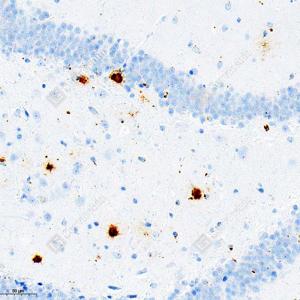

IHC检测beta Amyloid 1-40蛋白(货号 GB150027). 样品: 小鼠FAD4T转基因小鼠脑组织, 4%多聚甲醛 (货号G1101) 固定12-24小时. 抗原修复: 柠檬酸抗原修复液(干粉, pH 6.0) (G1201), 高压锅均匀喷气计时2分钟. —抗: 1: 500稀释, 4℃ 孵育过夜. 二抗: S-vision免疫组化多聚二抗(山羊抗兔),即用型 (货号G1302), 室温孵育20分钟. |